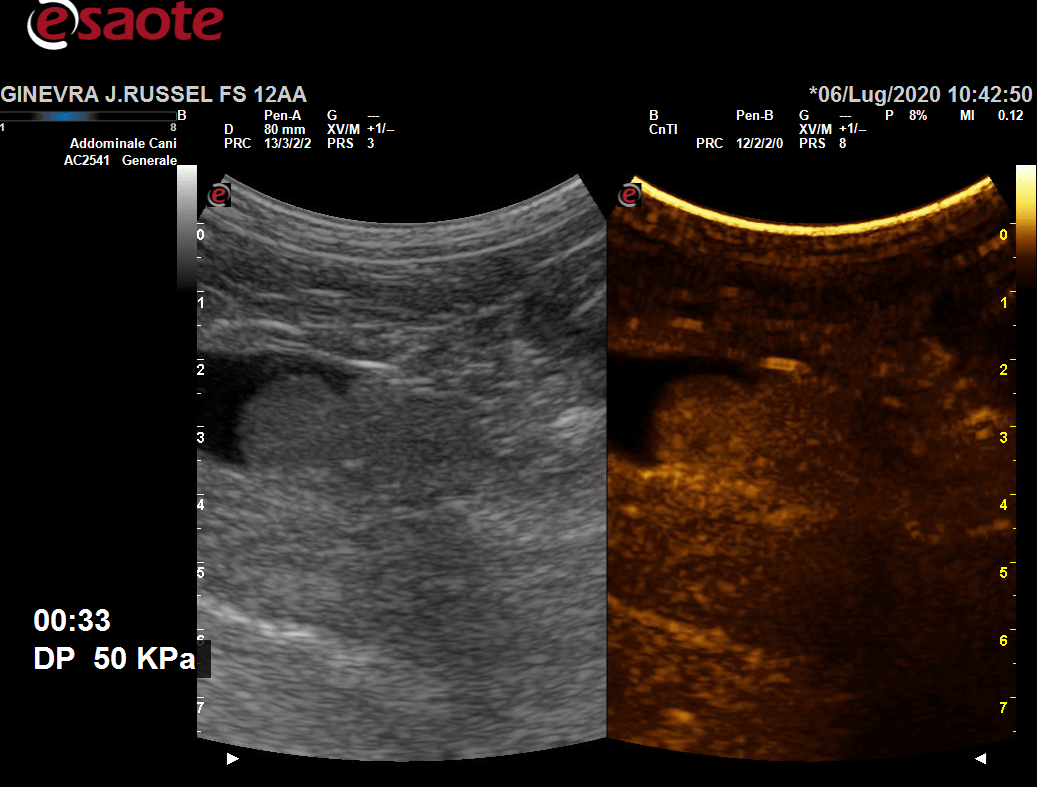

Effettuate tramite l’ecografo italiano Esaote My LabOmega, ecco quali sono le ecografie di cui ci occupiamo:

- esame CEUS ecografia con mezzo di contrasto.